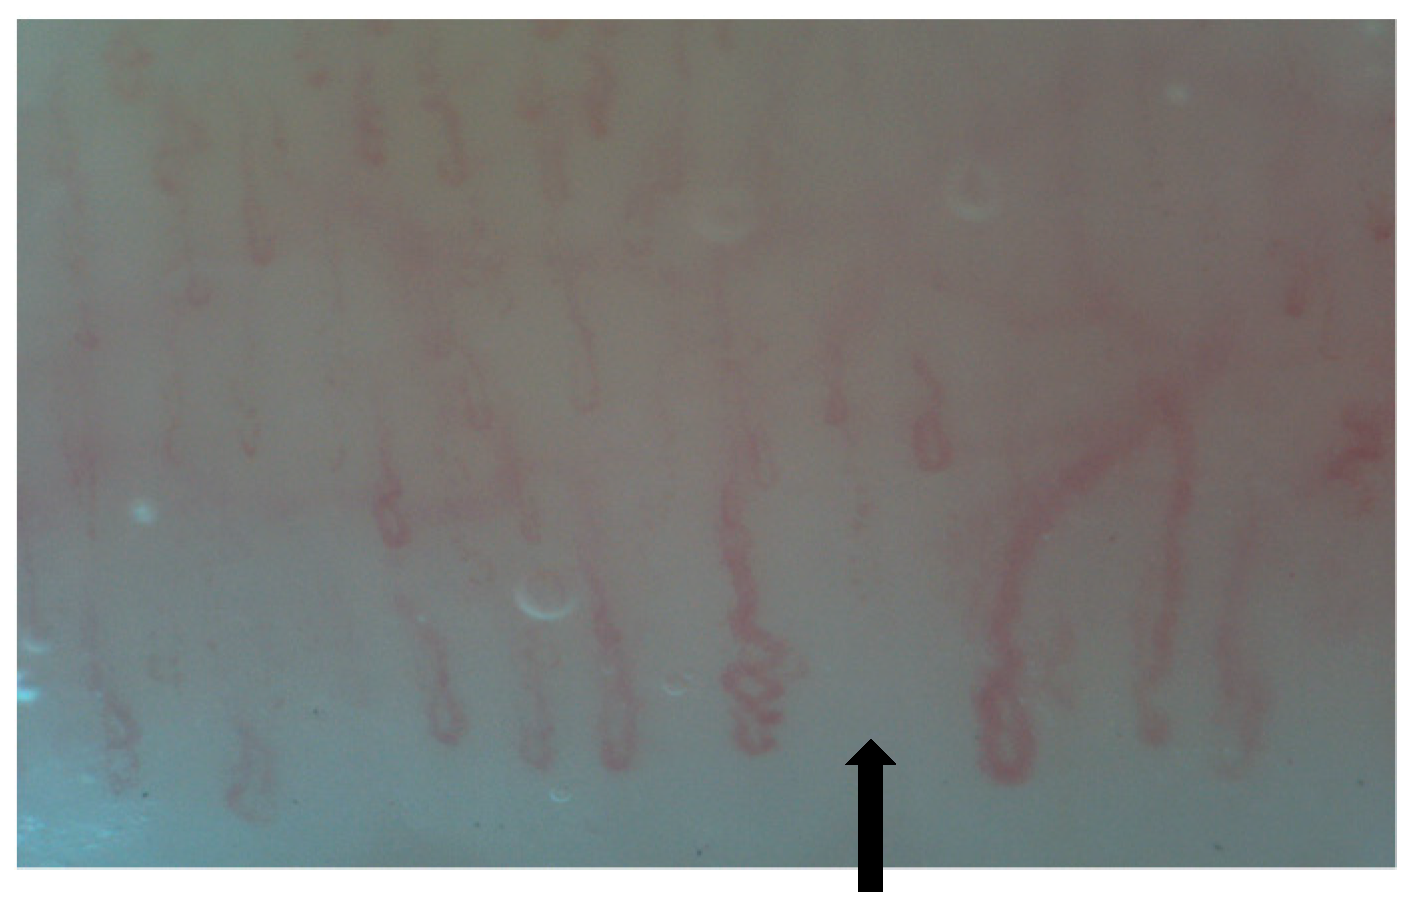

2. Normal Capillary Pattern